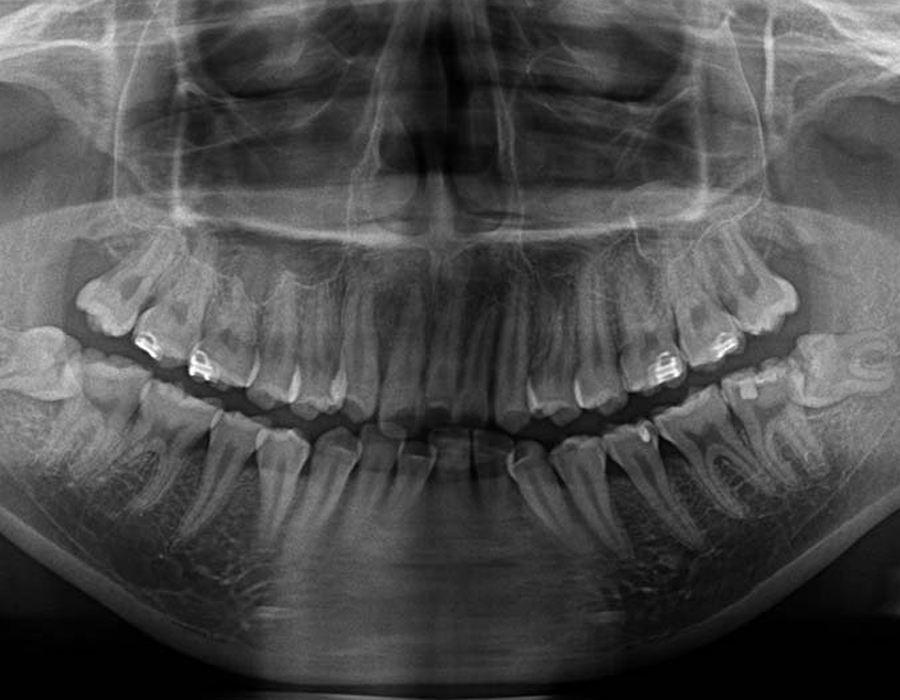

STEP 02検査&検診

短時間で安全に親知らずを抜歯するためには、事前の画像検査が欠かせません。CT撮影により、親知らずや顎の骨の状態を詳しく知ることができます。その上でお口の中を拝見します。現状と歯科医としての意見をお伝えし、患者様と話し合いながら、抜歯を行うのか、残して経過観察に留めるか決定します。

検査&検診